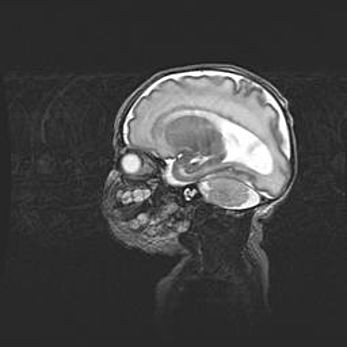

Открытая гидроцефалия.

Возраст: 9 месяцев 12 дней

Вес: 6800 г

Пол: мужской

Окружность головы: 41,5 см

Срок гестации: 28 недель

Гидроцефалия головного мозга у новорожденных имеет характерный признак: опережающий рост окружности головы приводит к визуально хорошо определяемой гидроцефальной форме сильно увеличенного в объёме черепа. Детские неврологи определяют следующие симптомы гидроцефалии у грудничков: выбухающий напряжённый родничок, частое запрокидывание головы, смещение глазных яблок к низу.